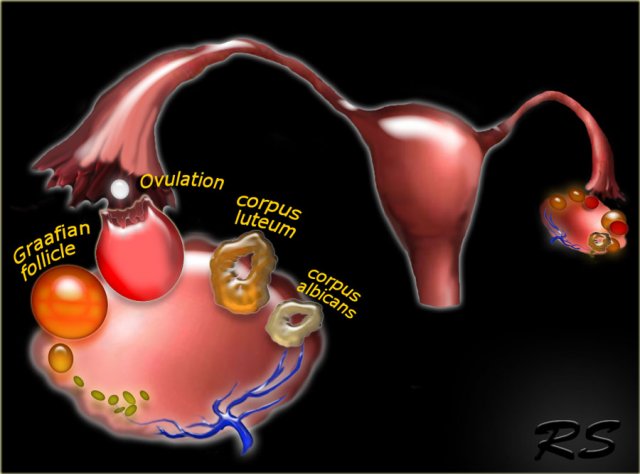

The normal ovary contains over two million primary oocytes at birth, about 10 of which mature each menstrual cycle.

Of the 10 Graafian follicles that begin to mature, only one becomes the dominant follicle and grows to a size of 18-20 mm by mid-cycle, when it ruptures to release the oocyte.

The other nine follicles become atretic and fibrous.

After release of the oocyte, the dominant follicle collapses, and the granulosa cells in the inner lining proliferate and swell to form the corpus luteum of menstruation.

Over the course of 14 days the corpus luteum degenerates, leaving the small scarred corpus albicans.